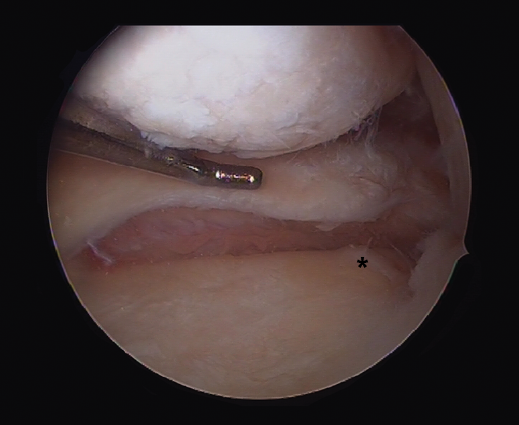

Other tests that contribute to the diagnosis are stress valgus radiographs (local anesthesia infiltration is advised in order not to underestimate the test), magnetic resonance imaging (MRI) and arthroscopic exploration (Figure 1).

Figure 1. Arthroscopic view through the anterolateral port of a positive drive-through sign with abnormal aperture of the internal compartment secondary to insufficiency of the medial collateral ligament. Right knee.